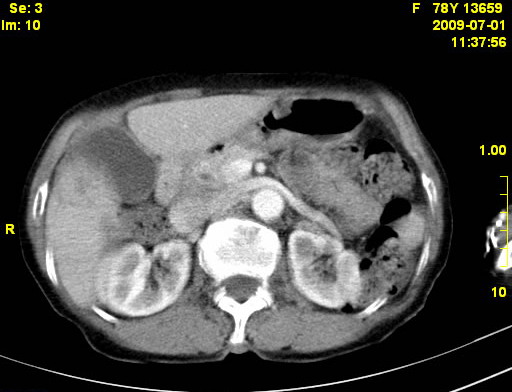

以下是引用zjzjr在2009-7-3 11:02:00的发言:[br]动脉期不均匀强化,门脉期及延迟期强化明显,肝门部见肿大淋巴结影,肝内胆管扩张.考虑肝右叶前段胆管细胞癌伴肝门淋巴结转移,胆内胆管扩张.慢性胆囊炎.

以下是引用dsl555在2009-7-4 10:59:00的发言:[br]考虑肝右叶前段胆管细胞癌伴肝门淋巴结转移,胆内胆管扩张.慢性胆囊炎. [br][br]支持。